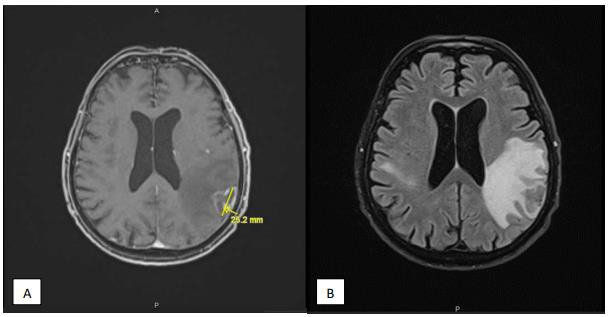

Seven months later, the patient presented to the emergency for confusion, agitation, Brocca aphasia, diplopia and left mydriasis. Biology showed essentially lymphocytopenia (160 ly/ μl). Brain MRI on 13/12/2019 showed at least eight intra-axial supratentorial lesions. Three of them were supracentimetric with marked perilesional edema predominant in the left parietal (Figure 1), compatible with secondary lesions (no argument for lymphoma or PML). In 2018, toxoplasma serology was IgG positive. An exhaustive bacteriological assessment was carried out with, among others, search for cryptococcus, herpes simplex and toxoplasma gondii in CSF: negative. Thereby, a brain biopsy was performed. It showed a florid toxoplasmosis, associated with a major chronic inflammatory reaction (encephalitis) and with a range of supracentimetric ischemic necrosis probably secondary to significant chronic hypertrophic meningitis with vascular lesions notably comprising partially recanalized thromboses. Inflammation begins on the wall of meningeal vessels (vasculitis or more probably inflammation secondary to the phenomena of thrombosis). The results highlight cerebral toxoplasmosis (Figure 2). Treatment with high dose TMP/SMX was started. After six days of treatment, TMP/ SMX was stopped because of major hyponatremia and shifted to clindamycin 600 mg four times a day and pyrimethamine 75 mg once daily for a total duration of 42 days. An improvement in the patient’s neurological condition was gradually observed.

Brain imaging with computed tomography or magnetic resonance is essential for the diagnosis of toxoplasma lesions. However, MRI should be used as the initial choice if there is a high clinical suspicion, due to its greater sensitivity than CT [10].

With the advent of new monoclonal antibodies and the associated lymphocytopenia, there is an evolving need of recommendation for prevention and management of opportunistic infections in patients receiving these agents. It is essential to think of opportunistic cerebral infections even at distance from therapy. Indeed, early suspicion and prompt treatment during the initial phase of cerebral toxoplasmosis reduce the risk of neurological sequelae and death. Brain MRI and prompt brain biopsy can provide rapid diagnosis and adequate treatment of cerebral toxoplasmosis.